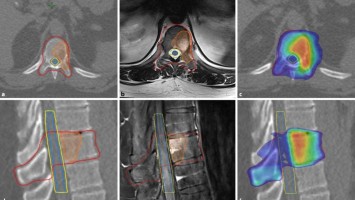

Stereotaktische Strahlentherapie bei Prostatakrebs intensiv geprüft

Mit Hilfe der PSMA-PET/CT lassen sich Patienten mit Prostatakarzinomen identifizieren, bei denen eine lokale Therapie möglich ist und die z.B. von einer stereotaktischen Radiotherapie profitieren könnten. Die aktuelle Evidenz dazu wurde auf dem DGHO-Kongress vorgestellt.